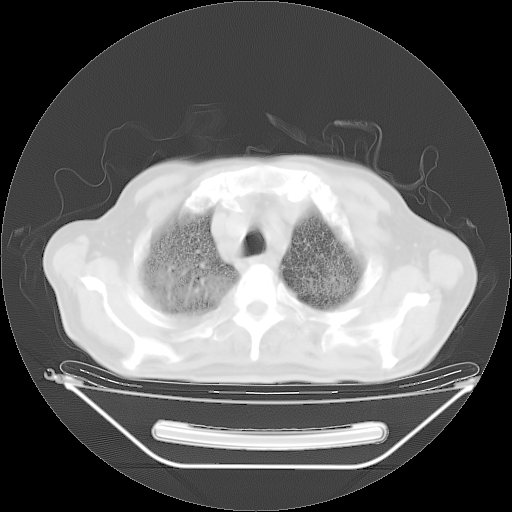

今天复查肺部CT,发现双肺广泛磨玻璃样改变。所以我把3月19日和5月9日相隔50天的肺部CT上传。请大家会诊。

2009年3月19日肺部CT片。

2009年3月19日肺部CT

5月9日肺部CT(在4月27日齐鲁医院肺部CT描述部分肺组织磨玻璃样改变,12天后肺组织广泛磨玻璃样改变)

大致读了系列胸部CT:纵隔窗无明显异常,肺窗:从4、27至今:主要是双肺中下野外带可见毛玻璃样改变,目前处于急性肺泡炎阶段,至于原因考虑1、结替组织或胶原血管性疾病所致?2、恶性疾病如恶组在肺部所致的表现或细支气管肺泡癌?3、药物或其它原因如肺蛋白沉着症所致肺泡炎目前不太可能?总之,明天就去请我院的呼吸科、感染科、血液科和临免专家会诊哈。